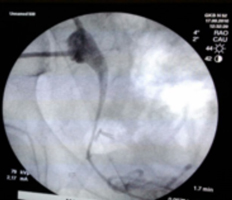

Пациентке первым этапом была выполнена пункционная нефростомия для обеспечения оттока из почечной лоханки.

При развитии таких урологических осложнений после ранее выполненного анастомоза донорского мочеточника с «родным» мочевым пузырем, лучшим вариантом в данной ситуации была признана операция по формированию анастомоза трансплантированной почки с родным, «нативным» мочеточником. Таким образом, была выполнена вторичная реконструкция мочевых путей лапароскопическим доступом. Наличие забрюшинного фиброза, различные варианты топографии между структурами трансплантированной почки и окружающими органами в какой-то степени ограничивают применение лапароскопических технологий, но наш первый опыт выполнения данной операции был успешным.

Время операции составило 240 мин. Кровопотеря минимальная. Пациентка активизирована на 2 сутки, дренажи удалены на 5 сутки. Выписана на 7 сутки, при выписке дисфункции трансплантата не наблюдалось.